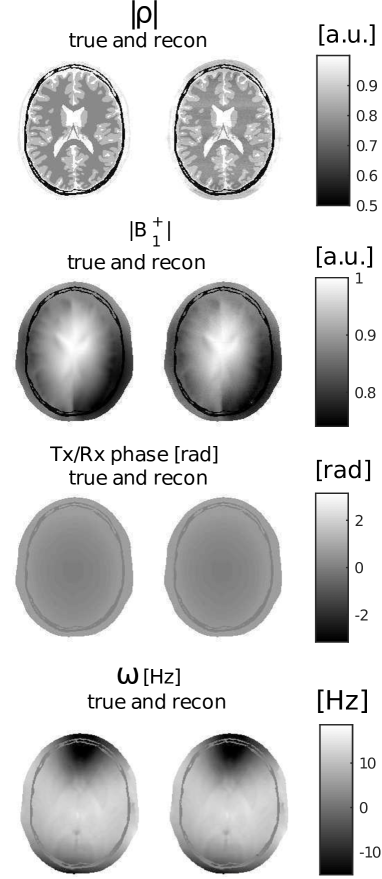

The amplitude and phase maps of the transmit RF field are obtained from a numerical electromagnetic simulation of a 3T headcoil driven in quadrature. Without loss of generality, a uniform receive sensitivity is assumed in this example. The off-resonance map is taken from [21] and is scaled to fit the range of Hz in the head (see the bottom of Fig. 7).

Beside , and , also the transmit field profile and off-resonance map are reconstructed; they are displayed in Figures 6 and 7. They closely agree with the true values. In Table 2, the mean values and corresponding variations over each tissue type are reported and show high precision.

The root-mean-squared-errors (RMSE) for the and maps are also very small, namely:

The reconstruction time is about 90 minutes. The median number of performed iterations as calculated over all parallel reconstruction processes is 13.

The standard deviations estimated by MR-STAT for and are shown, respectively, in Fig. 6(b) and Fig. 6(d). For comparison, the actual error maps, respectively defined as and , are also reported and they show clear similarities.